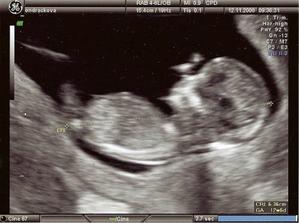

15.9.08 HCG 349,5 IU ;) hurrrrrrrraaaaaaaaaaa!!!

asi budeme mit v kvetnu 09 miminko!!!!!!!!!!!!!!!!!